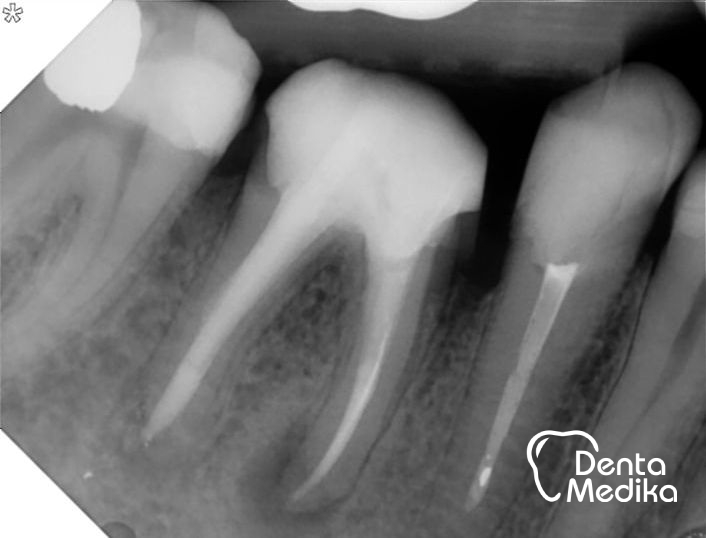

Na prvním obrázku je vidět kostní defekt, zejména u zadního kořene a v prostoru mezi kořeny (tmavá místa) - rentgen je pořízen ihned po endodontickém ošetření. Na druhém obrázku je stav při kontrole za půl roku. Pacient zároveň chodil na ošetření k dentální hygienistce. Výsledkem je pevná kost bez zánětu, která obklopuje hroty kořenů a dostává se i do mezikořenového prostoru. Lze předpokládat ještě další zlepšení stavu v závislosti na čase. (Práce Dr. Holubjakové, plněno ještě starší metodou - Laterální kondenzace. Dnes již používáme, k prasknutí kořene méně rizikovou, metodu Vertikální kondenzace za tepla, pomocí přístrojů typu BeeFill.)